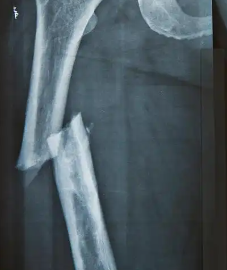

무릎 통증은 종종 로화와 관련이 많다. 그런데 최근에는 전세계적으로 젊은이들중에서도 무릎 통증을 호소하는 사람들이 증가하고 있는 것으로 나타났다.